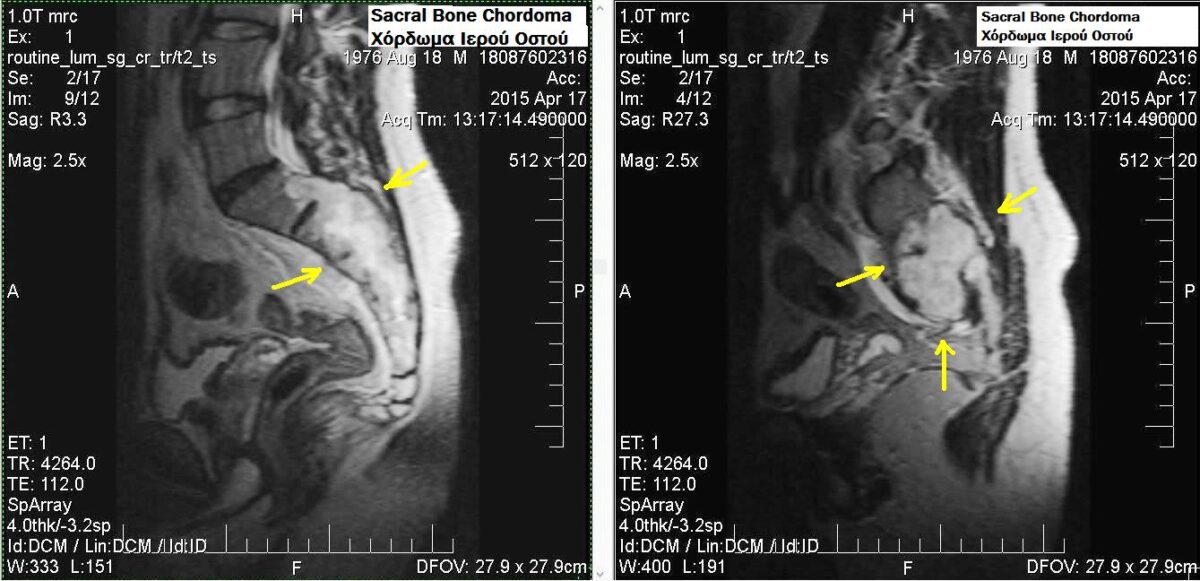

Chordomas can arise from bone in the skull base and anywhere along the spine. The two most common locations are cranially at the clivus and in the sacrum at the bottom of the spine.

Sacral chordoma is presented with chronic low back pain.